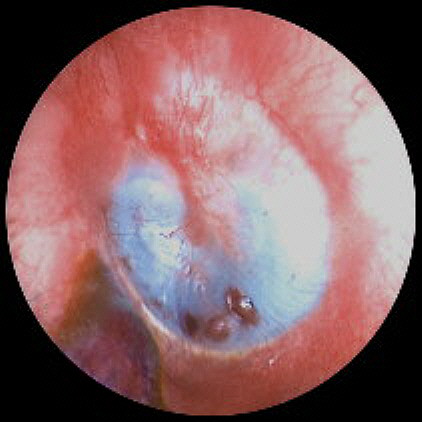

Figure 3. Initial surgical exposure shows residual impression material in the operative field. Click image for full size view.

It was initially felt visually that the incudostapedial complex was encased

in silicon. As the silicon was retracted inferiorly from this area, however, it

was seen that the silicon extended to/and abutted against the incudostapedial

complex but did not surround and encase the ossicles. The ossicular chain was

therefore able to be kept intact throughout the procedure. All posterior and

inferior areas of the tympanum were able to be cleaned of the silicon using

this piecemeal removal. At this point additional photographs (Figures 4-6) were taken.